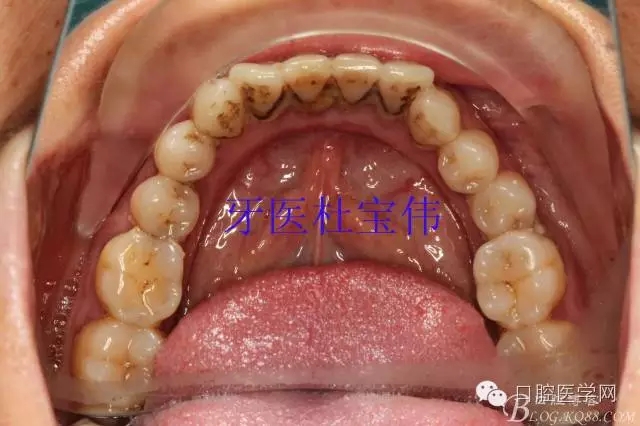

病例二術(shù)前照片